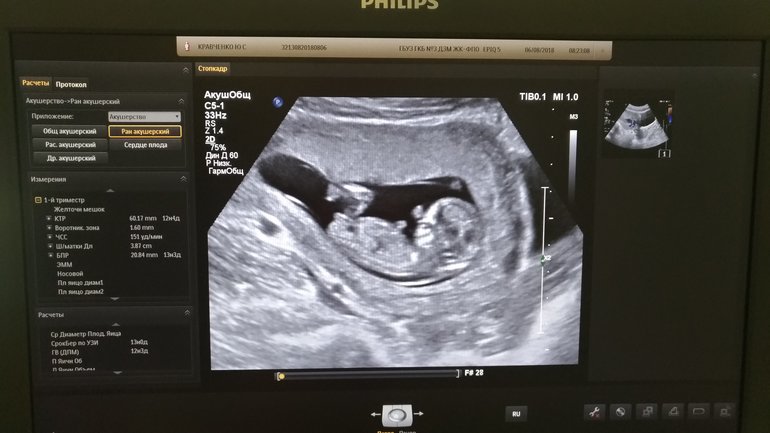

Первый скрининг

Ура, дожили! До этого дня, если честно, даже сомневалась, а беременна ли я. Безосновательно конечно - все признаки на месте, и не в первый раз уже, но все равно как-то не верилось. Даже кроме мамы не сказала никому (ну это я, у мужа то даже самые дальние родственники оповещены 😡). А сегодня и сердечко впервые услышала, и посмотркла на маленького спящего человечка - крутяк! И это все у меня внутри! Ну чудеса же... Дабы не потерять, оставлю тут все цыфры и замеры. А вообще, сказали все в норме. Делали, кстати, в роддоме в Зеленограде, так что если кому интересно, спрашивайте)